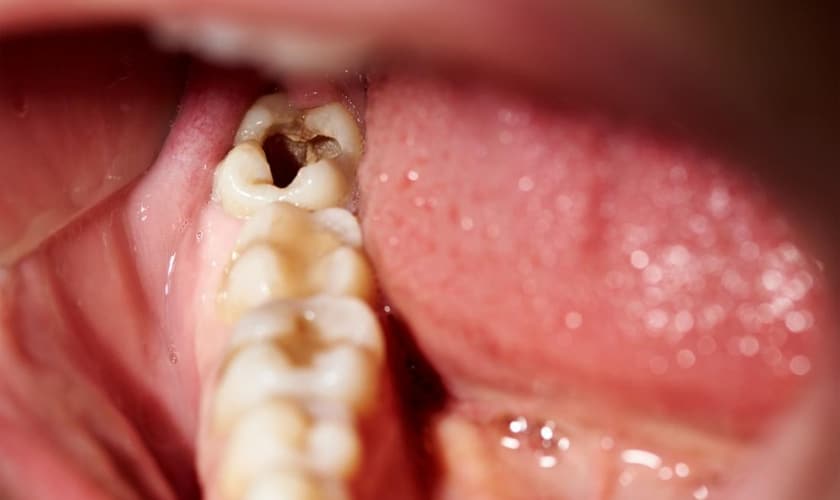

1. Sâu răng khôn và răng kế cận

- Răng khôn mọc lệch hoặc mọc ngầm khiến việc vệ sinh trở nên khó khăn, thức ăn dễ mắc kẹt.

- Đây là môi trường lý tưởng cho vi khuẩn phát triển, gây sâu răng khôn.

- Nếu không điều trị kịp thời, sâu răng có thể lan sang răng số 7, gây tổn thương răng bên cạnh.

3. Sâu răng và hôi miệng

- Tích tụ thức ăn và vi khuẩn quanh răng khôn khiến răng số 7 hoặc răng khôn bị sâu.

- Viêm nhiễm kéo dài là nguyên nhân gây hôi miệng dai dẳng, khó cải thiện nếu răng khôn mọc sai vị trí không được xử lý.